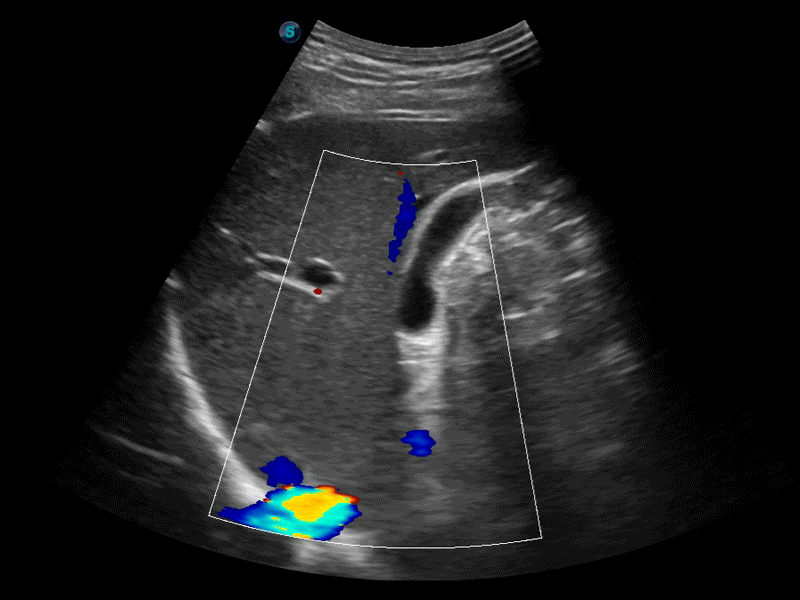

彩色多普勒超声诊断系统

• SR Flow高分辨率血流成像技术

高分辨率血流成像技术提高了对低速血流信号的检测能力。在提高空间分辨率的同时,也克服了血流外溢现象,为用户提供更加真实的血流动力学信息。

临床图像